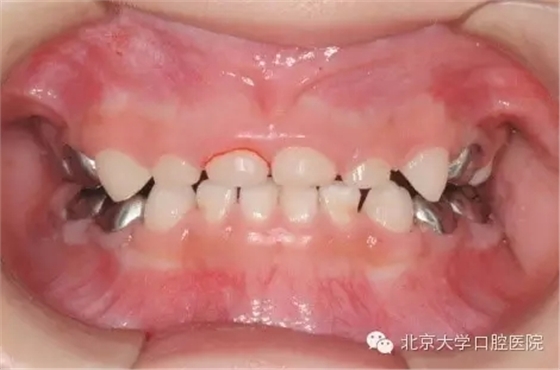

全麻治療中醫(yī)生對(duì)缺損較大的后牙經(jīng)常會(huì)采用“預(yù)成冠”修復(fù)的方法,預(yù)成冠由不銹鋼制成,可以很好的恢復(fù)牙齒的外形并預(yù)防牙齒及充填體折斷,并不影響牙齒替換。